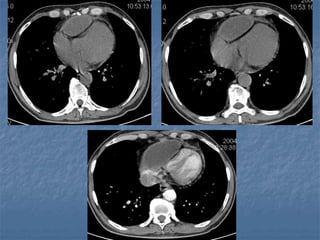

RUPTURA TRAUMÁTICA DE LA AORTA

RX DE TORAX:

1. ENSANCHAMIENTO DEL MEDIASTINO.

2. BORRAMIENTO DEL BOTON AORTICO.

3. DESVIACION DE TRAQUEA A LA DERECHA.

4. BORRAMIENTO DE LA VENTANA AORTOPULMONAR.

5. DEPRESIÓN DEL BRONQUIO IZQUIERDO.

6. DESVIAICIÓN DEL ESÓFAGO A LA DERECHA.

7. ENSANCHAMIENTO DE LA FRANJA PARATRAQUEAL.

8. ENSANCHAMIENTO DE LA INTERFASE PARAVERTEBRAL.

9. GORRO PLEURAL

10. HEMOTÓRAX IZQUIERDO.

11. FRACTURA DE 1A. O 2A. COSTILLAS O DEL OMOPLATO.

AORTOGRAMA

?

RUPTURA TRAUMÁTICA DELA AORTA RX DE TORAX: 1. ENSANCHAMIENTO DEL MEDIASTINO. 2. BORRAMIENTO DEL BOTON AORTICO. 3. DESVIACION DE TRAQUEA A LA DERECHA. 4. BORRAMIENTO DE LA VENTANA AORTOPULMONAR. 5. DEPRESIÓN DEL BRONQUIO IZQUIERDO. 6. DESVIAICIÓN DEL ESÓFAGO A LA DERECHA. 7. ENSANCHAMIENTO DE LA FRANJA PARATRAQUEAL. 8. ENSANCHAMIENTO DE LA INTERFASE PARAVERTEBRAL. 9. GORRO PLEURAL 10. HEMOTÓRAX IZQUIERDO. 11. FRACTURA DE 1A. O 2A. COSTILLAS O DEL OMOPLATO. AORTOGRAMA